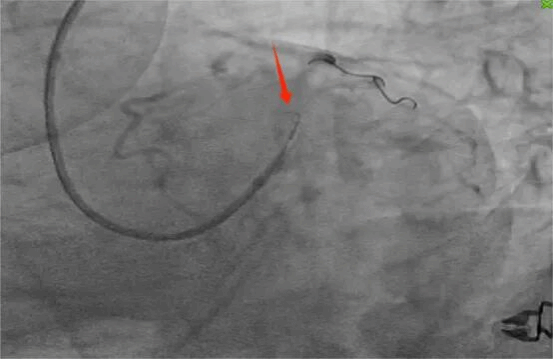

1. 导丝通过:精准将导丝送入罪犯血管;

(精准操作瞬间)